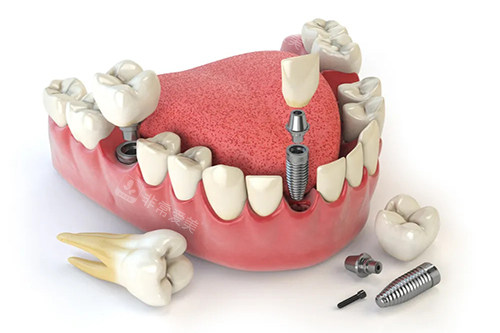

牙齿种植卡通示意图

牙齿种植牙模型卡通示意图

在复杂修复领域,像牙齿种植、牙齿正畸等,医师团队会根据患者的具体情况,结合较高的技术和设备,制定科学合理的修复方案。